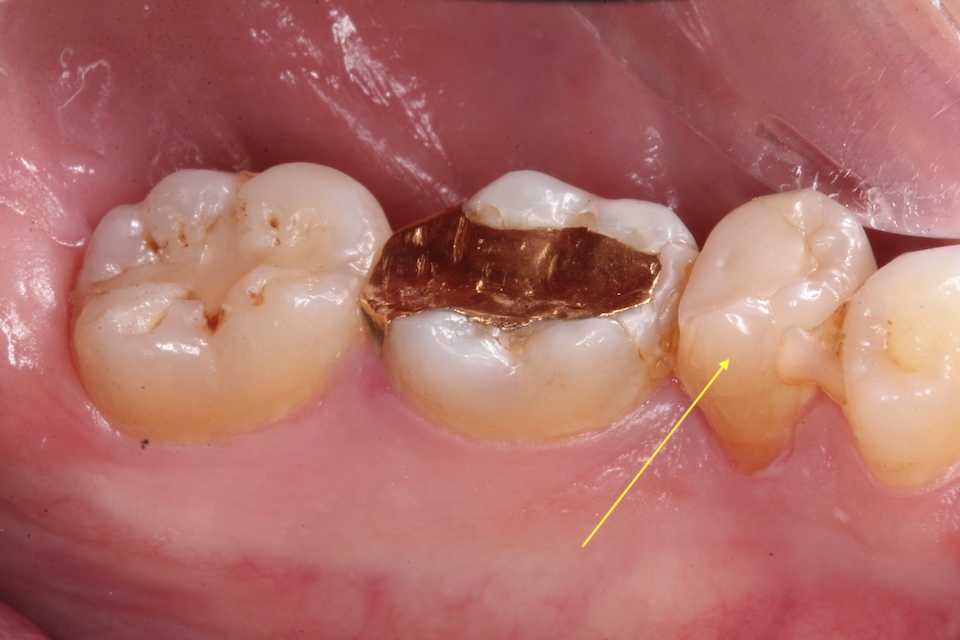

30代男性、右下5、Per

2年半ぶりにいらっしゃったので、口腔内規格写真での今日の画像です。

神経を取っているのでクラックは入りやすい。いずれ補強冠が必要になるだろう。

骨植は非常に良く問題なく生着・機能している。

歯列固定は1箇所を除いて脱離していたが、その1箇所も除去した。